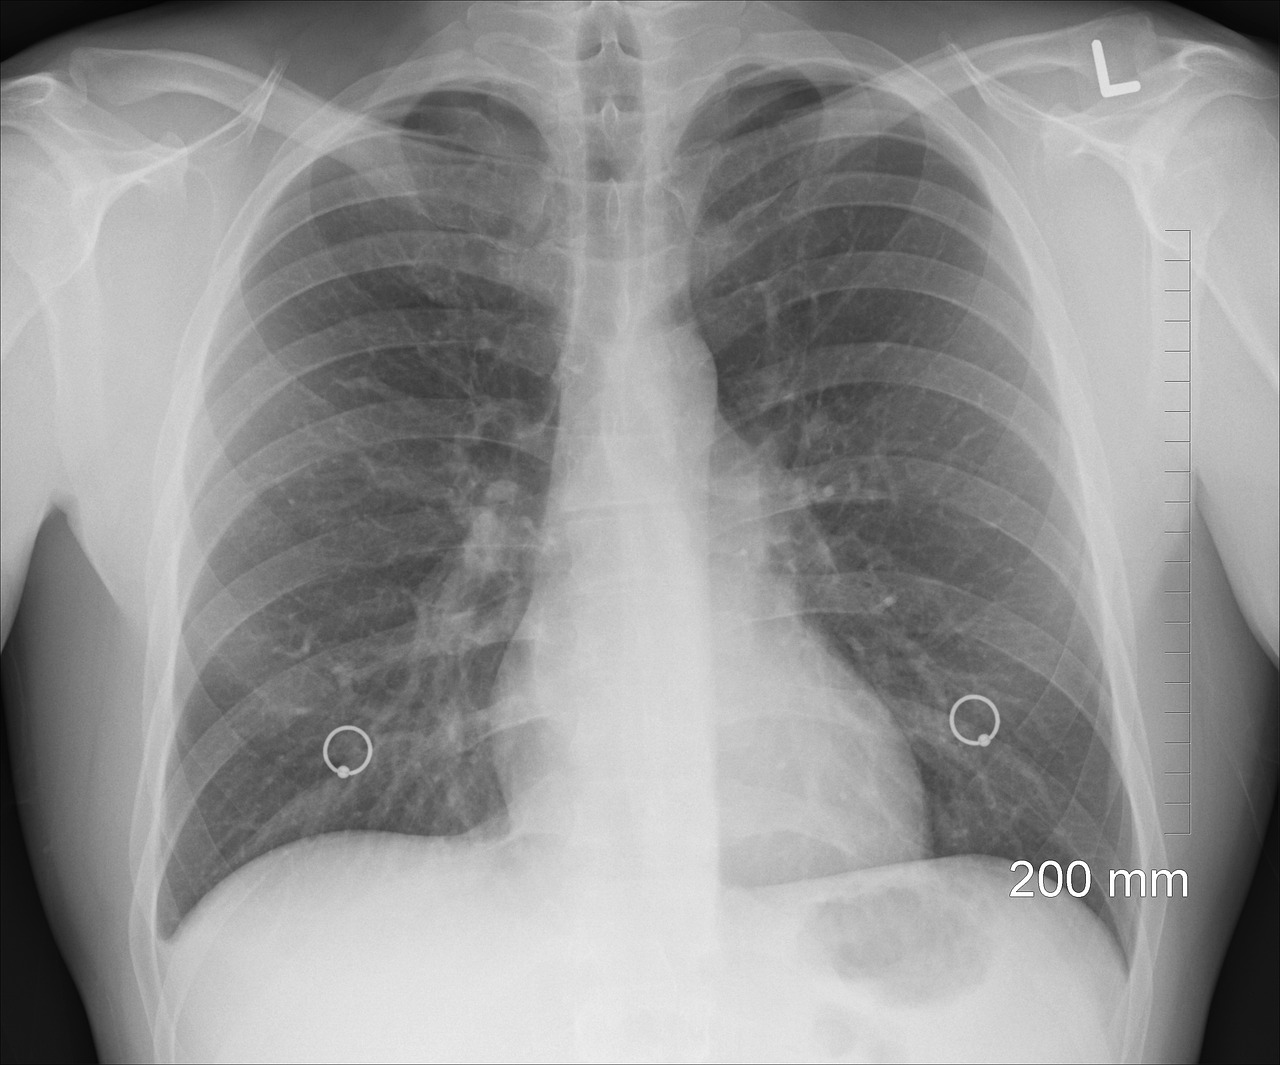

① 흉부 X선 촬영

X선 검사방법으로는 실제 크기로 촬영하는 흉부 직접촬영과 70㎜, 100㎜ 크기의 축소된 사진으로 찍는 간접촬영이 있는데, 여러 사람을 집단으로 검사할 경우에는 간접촬영을 많이 이용합니다.

소견에 따라 초감염 결핵과 재활성화 결핵으로 나뉘며 흔히 전자는 소아 결핵, 후자는 성인 결핵으로 분류하기도 하며 인체면역결핍 바이러스(HIV) 감염자는 초감염 결핵 소견이 주로 나타나는 것으로 알려져 있습니다.

③ 흉부 전산화 단층촬영(CT)

임상적으로 의심은 되나 흉부 X선 검사만으로 결핵의 진단이 힘든 경우에 전산화 단층촬영(CT)이 이용됩니다.

CT는 오래된 섬유화 병변과 새로운 활동성 병변을 구분하는 데 도움을 주는데, 특히 소세기관지나 소세기관지 주위의 병변은 결핵이 시작됨을 특징적으로 보여줍니다

그 외에도 CT는 공동, 흉곽 내 림프절 병증, 좁쌀 결핵(결핵균이 피를 타고 전신으로 퍼져나가 여러 장기에 염증을 일으킨 상태로 마치 좁쌀처럼 미세한 병변이 전신에 나타나는 것), 기관지 확장증, 기관지 협착, 흉막 질환을 진단하는데 민감도가 높고 결핵종 내의 석회침착 여부 판정에 특히 유용합니다.